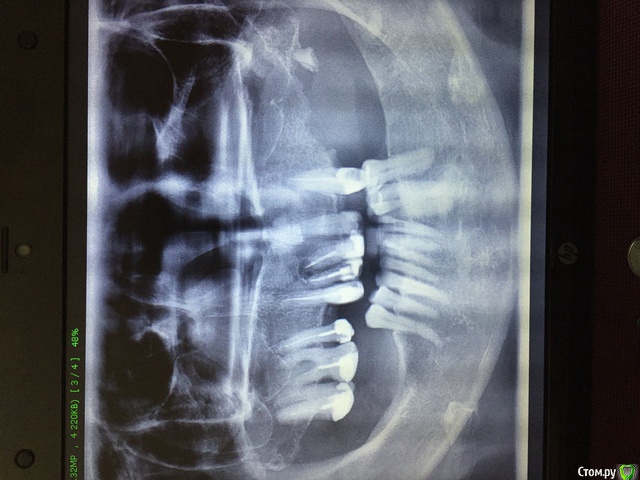

Olga40 Опубликовано 10 апреля, 2019 Поделиться Опубликовано 10 апреля, 2019 (изменено) Добрый день! Уже два года постоянный насморк, у лора была проблемы не видит. Подскажите, пожалуйста может ли это быть связано с зубами? И можно ли как то спасти и какие зубы? Или все таки полное протезирование? Прошу прощения, фото перевернуть не получается Изменено 10 апреля, 2019 пользователем Olga40 Ссылка на комментарий

red_butler Опубликовано 10 апреля, 2019 Поделиться Опубликовано 10 апреля, 2019 сделайте стоматологическую Кт с придаточными пазухами носа Ссылка на комментарий